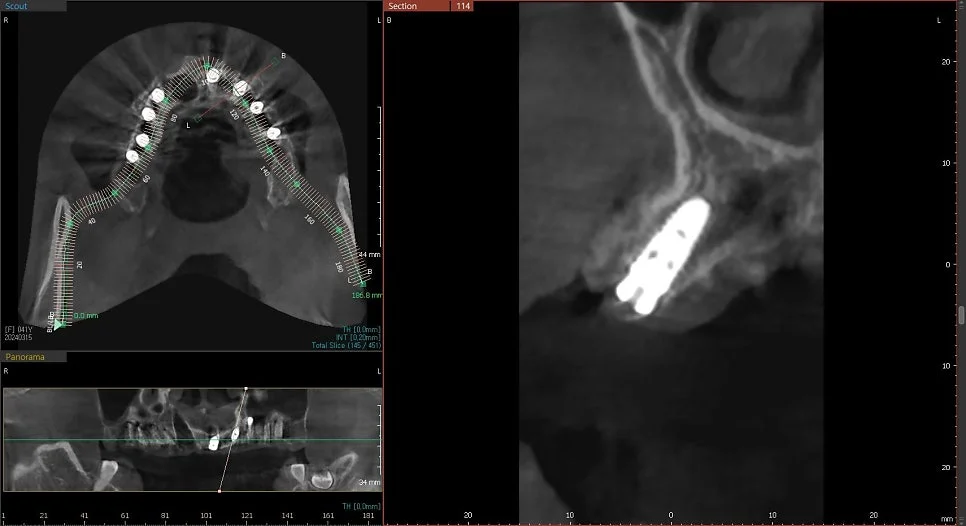

CBCT 단면 – 각 임플란트 개별 검증

CT 상에서 하얀색인 임플란트가 1. 온전히 뼈 안에 잠기게(1~2mm 깊게) 그리고 2. 가급적이면 입천장 쪽으로 식립되었다면 잘 심긴 임플란트입니다. (입술 쪽 뼈는 쉽게 흡수됩니다ㅜ)